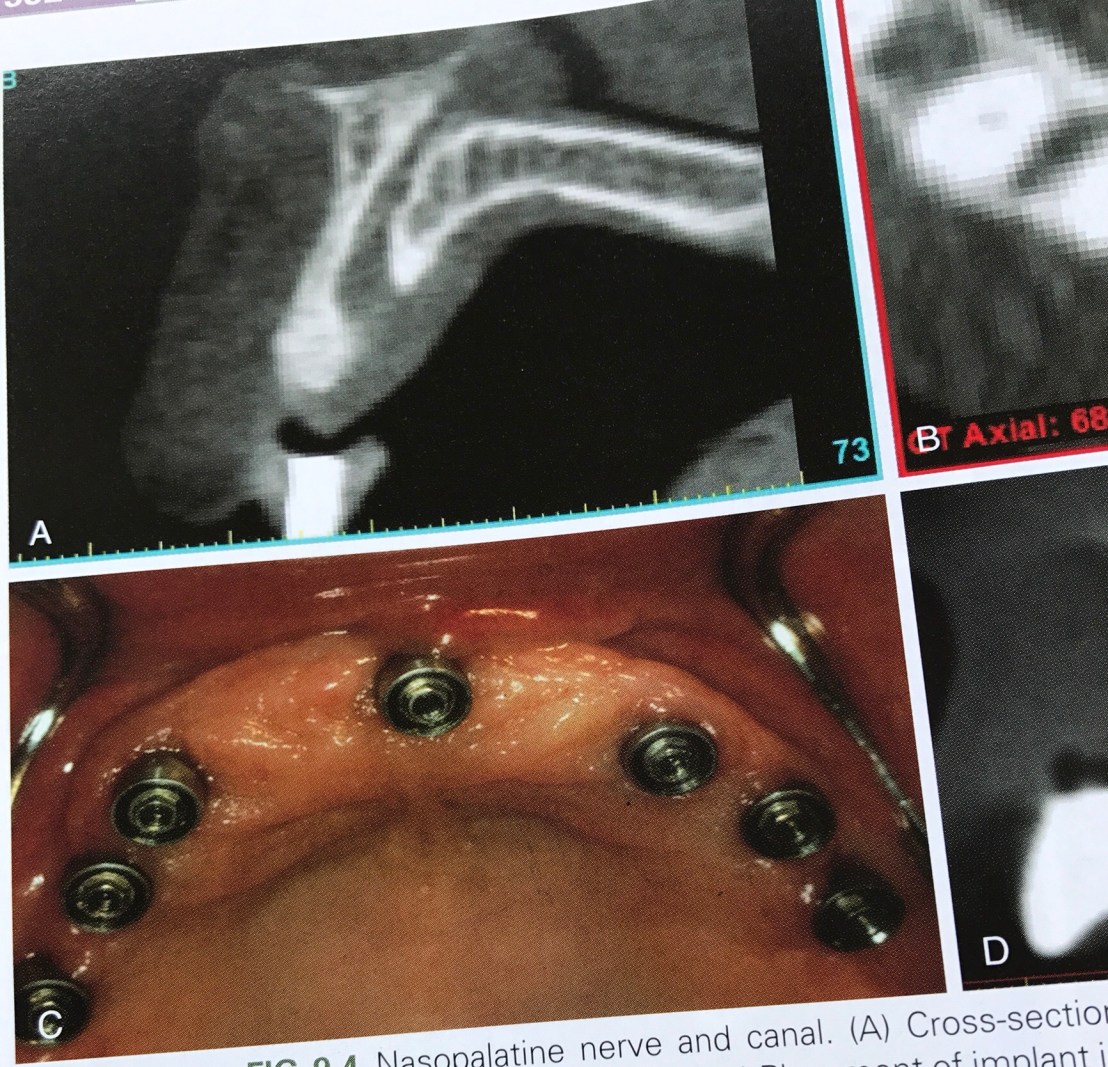

รูป A ด้าน Palatal คือ Nasopalatine canal ที่มีขนาดใหญ่มากในเคสนี้

รูป C คือ ความจำเป็นต้องฝัง Implant ในตำแหน่งนี้ครับ อันนี้คือ ฝังหลังจากย้าย Nerve ออกไปแล้วนะ

พบว่าตำแหน่งนี้ไม่ค่อยมีปัญหา อาจชาแบบ short term เพราะมักมี innervation จาก nerve อื่นเช่น Greater palatine nerve มาเลี้ยงภายหลัง

ให้ดูใกล้ๆ อีกครั้ง Nasopalatine canal ที่เชื่อม floor of nose กับ anterior palate